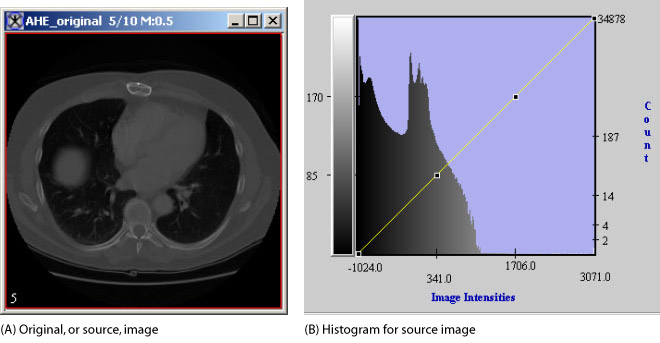

The reference image using the new histogram is similar to the source image; however, in areas where the source image had similar values, the reference image is enhanced. The reference histogram now stretches over a greater proportion of the possible image intensities (Figure 1).

Figure 1. Source image and histogram and reference images and histograms for reference images that were separated into 1 x 1, 2 x 2, and 3 x 3 regions

Note: All histograms shown in this section are in log scale in the vertical axis.

The histogram for the source image is very compact in structure; that is, it has a great number of darker pixels, but very few brighter pixels. In fact, the bottom-most intensity values make up almost all of the pixels' values in the image. Note, however, in the histogram of the reference image, the look-up table is more evenly spread than that of the histogram for the source image. Also, areas of low intensity and low contrast in the source image were correspondingly remapped in the reference image to areas of higher contrast and generally overall brighter values.